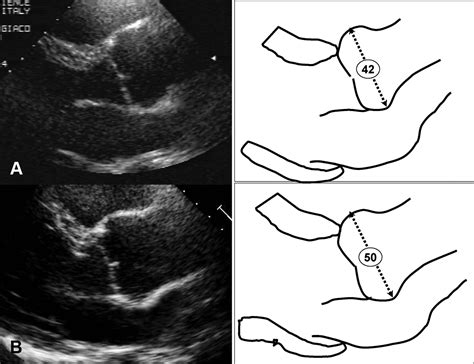

• Echocardiogram: This non-invasive test uses sound waves to create images of the heart and aorta, allowing the healthcare provider to measure the size of the aortic root and assess its function.